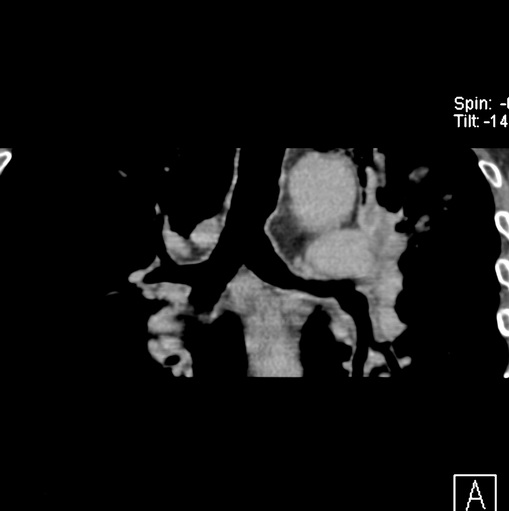

男性患者 81岁 咳嗽 咳痰 咯血

肿块贴近左肺门,包绕左上肺动脉,形态不规则。肿块增强扫描中度强化。纵膈内主动脉弓左旁间隙、气管隆突前、下间隙见多枚淋巴结影。综上考虑左侧中央型肺癌可能性大。图片没有完整上传,尤其是左肺上叶支气管分支层面没有上传,因此不好判断是叶支气管中断还是段支气管中断。另外,下图红色部分所示是“黏液支气管征”吗?